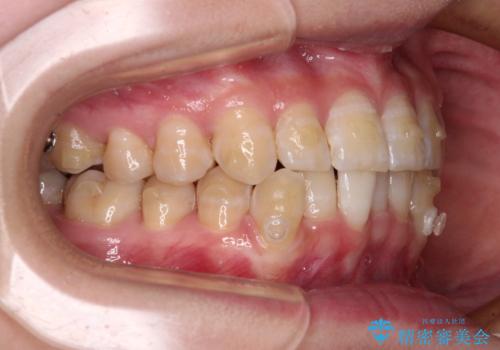

- 下顎の八重歯を気にして来院された患者様です。

マウスピース矯正でもワイヤー矯正でも対応可能であり、マウスピースによる治療を希望されたため、インビザラインを用いることとしました。

下顎前歯にデコボコが集中していたため、顎間ゴムによる後方移動とIPR(歯と歯の間を削ること)により歯列を整えることとしました。

下顎前歯のデコボコが集中しており、奥歯の咬み合わせは、上顎に対して下顎が前方位にある状態でした。下顎の歯列を後方へ移動させる治療はインビザラインの得意とするところですので、1年程度で無事に治療を終えることができました。